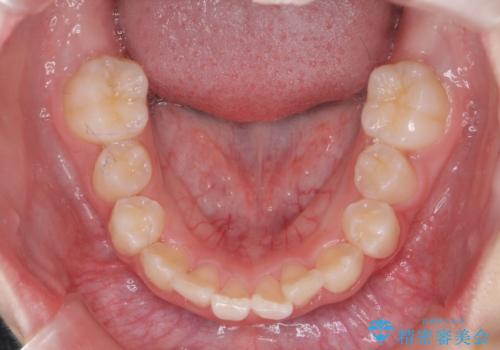

子供の出っ歯 生え代わりと成長期を利用して非抜歯で矯正

- 出っ歯を主訴に来院。

生え代わりを待ってから矯正を始めました。

特に右側のかみ合わせがずれていたため、上の奥歯を後ろに下げています。

下顎も前方に成長し、前歯のかみ合わせも同時に深かったのを浅くすることができました。